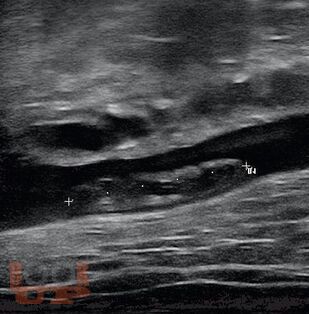

Современные методы диагностики заболеваний бассейна нижней полой вены

Учебное пособие содержит основные сведения о анатомии и физиологии венозной системы нижних конечностей, морфологии и патофизиологии данных заболеваний, современных методах диагностики. Рассчитано на ординаторов и слушателей ФДПО хирургических специальностей.